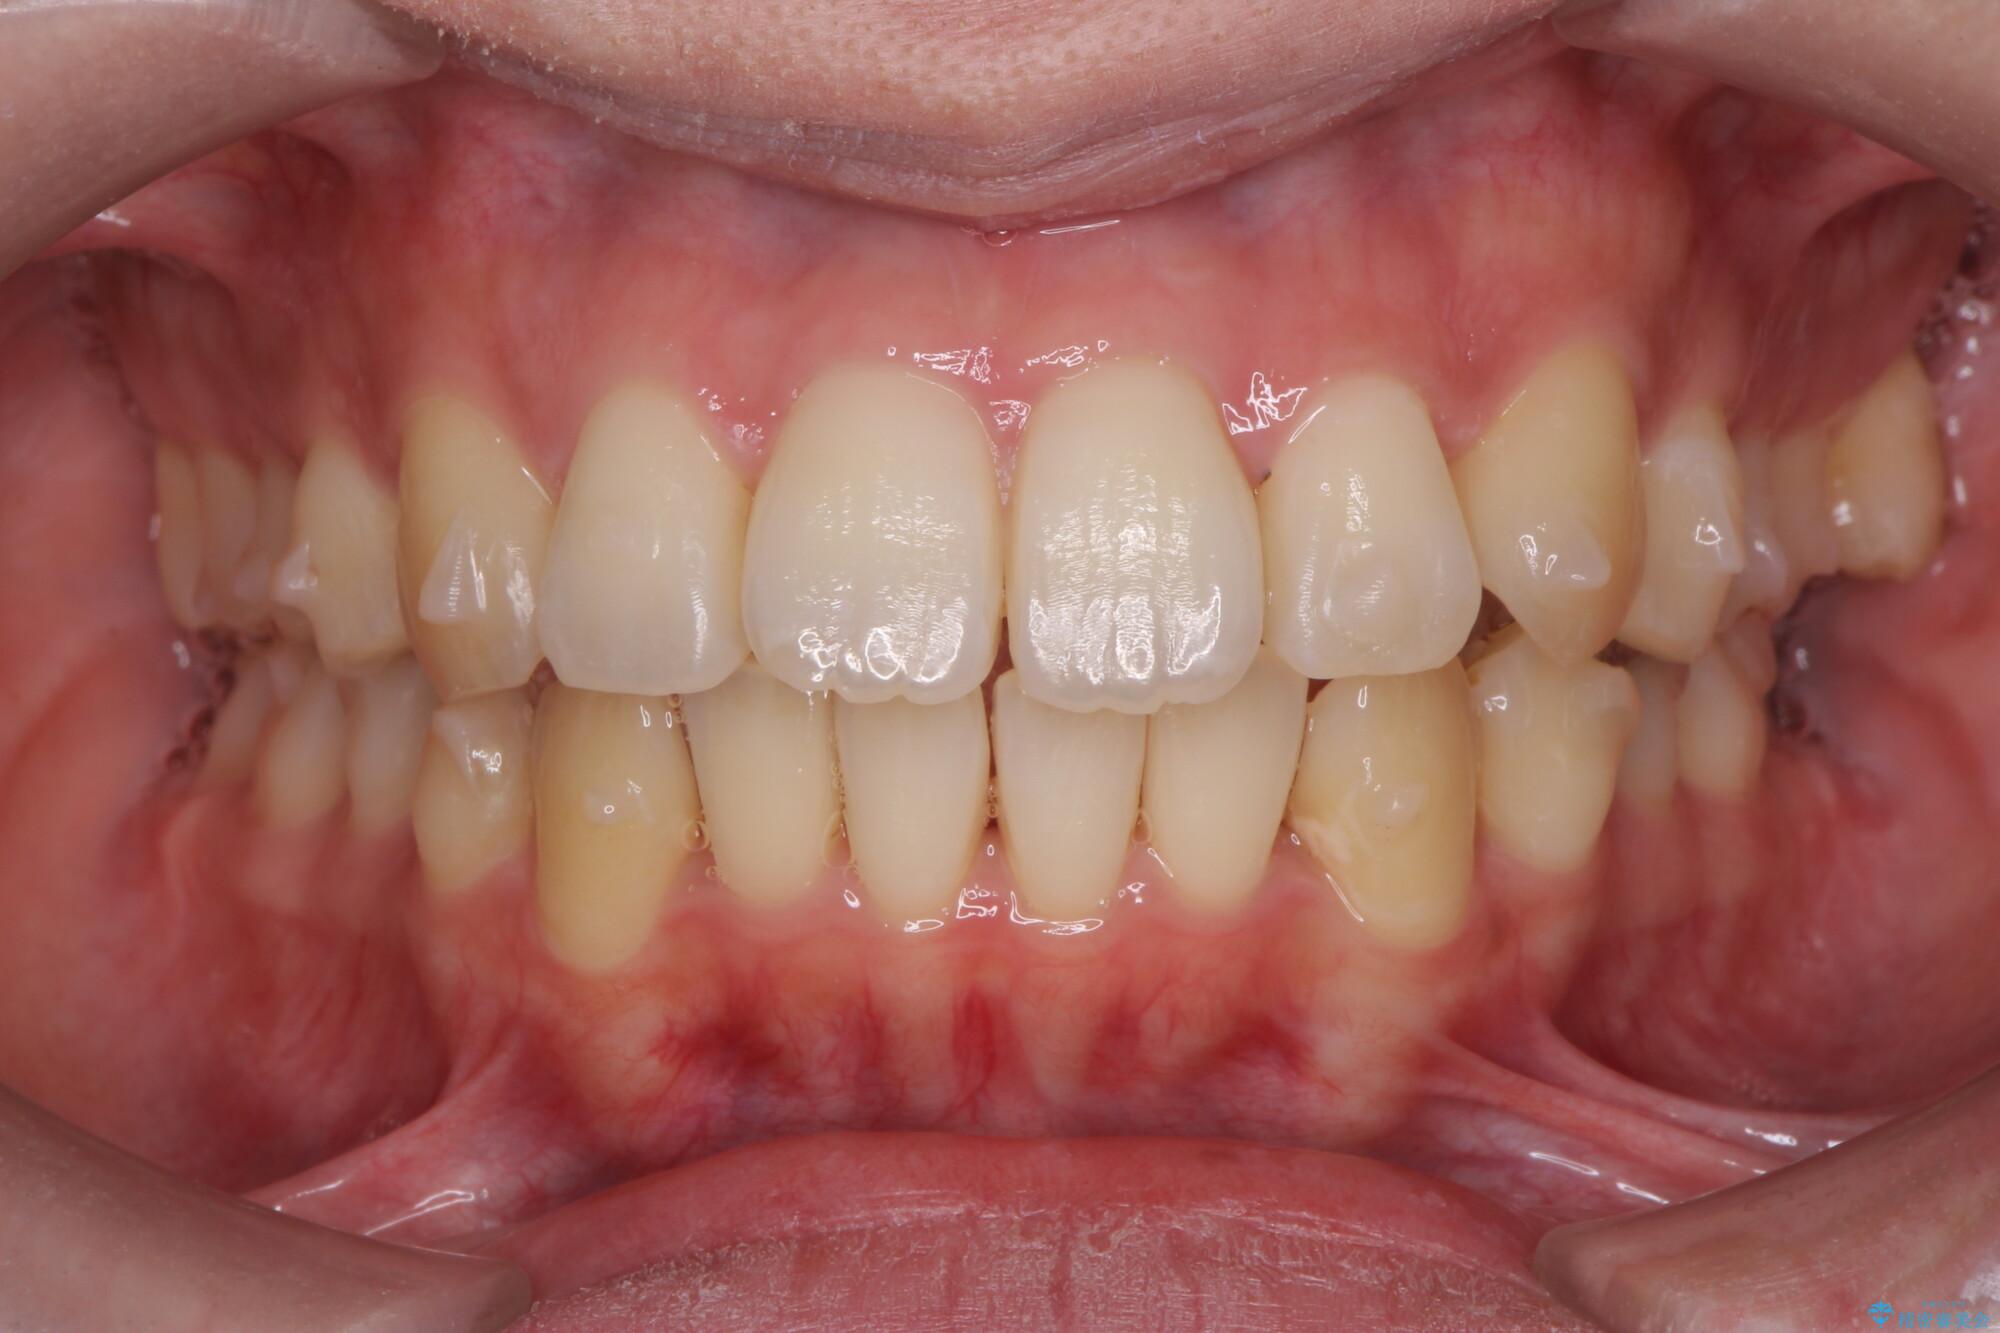

治療中

気になる犬歯のガタつきをマウスピース矯正で改善 治療中画像 気になる犬歯のガタつきをマウスピース矯正で改善 治療中画像 気になる犬歯のガタつきをマウスピース矯正で改善 治療中画像 気になる犬歯のガタつきをマウスピース矯正で改善 治療中画像